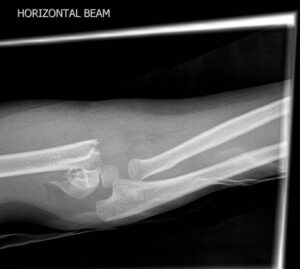

Bu radyografik gölge önde koronoid fossanın arka sınırı, arkada olekranon fossanın ön sınırı altta da kapitulumun üst kısmından oluşmaktadır. Doğru çekilmiş bir lateral grafide gözyaşı bulgusunun görülmesi gerekir.

Gözyaşı halkasında bozukluk ya da kum saati görünümünde belirsizlik olması uygun olmayan lateral grafi ya da orada bir kırık varlığını düşündürür.

[toggle title=”Anterior Humeral Hat” state=”close”]

Lateral grafide humerus ön yüzeyine paralel ve bitişik çekilen çizgi kapitulumun 1/3 ortasından geçmelidir.

Bu hattın öne ya da arkaya yer değiştirmesi suprakondiler humerus kırığını destekler.

Aynı zamanda suprakondiler kırık hattıyla beraber posterior yağ yastıkçığı bulgusu da görülmekte

Bununla beraber kırık hattı ve posterior yağ yastıkçığı bulgusu da seçilmekte.